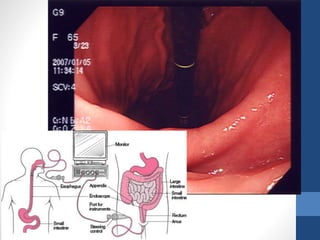

• Initial diagnostic examination for all patients

• Endoscopy should be performed immediately

after endotracheal intubation (if indicated),

hemodynamic stabilization, and adequate

monitoring in an intensive care unit (ICU)

setting have been achieved.

Endoscopy :

• Initial diagnosticexamination for all patients presumed to have UGIB • Endoscopy should be performed immediately after endotracheal intubation (if indicated), hemodynamic stabilization, and adequate monitoring in an intensive care unit (ICU) setting have been achieved. Endoscopy :